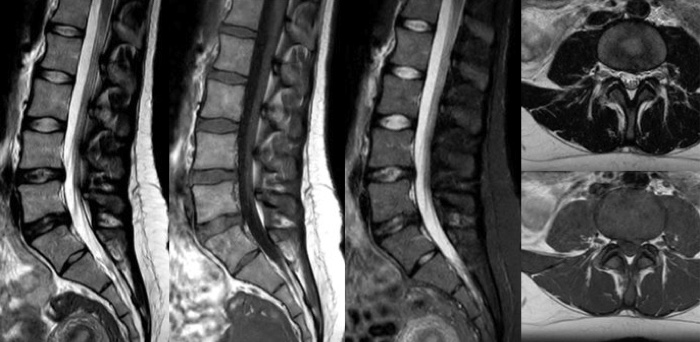

High quality diagnostic imaging

Our lightest Breeze coils bring versatility and create consistent high quality images for any anatomy.

Turn images into answers – 50% faster

Put time on your side with Compressed SENSE to reduce scan time up to 50%2 with virtually equal image quality. Create exceptional MR images with 60% higher resolution for confident diagnosis.

Quality images for quality diagnoses

Our lightest Breeze coils bring extraordinary versatility to imaging challenging anatomies and the smallest joints. A large 55cm field-of-view and premium SNR add to the exceptional image quality.